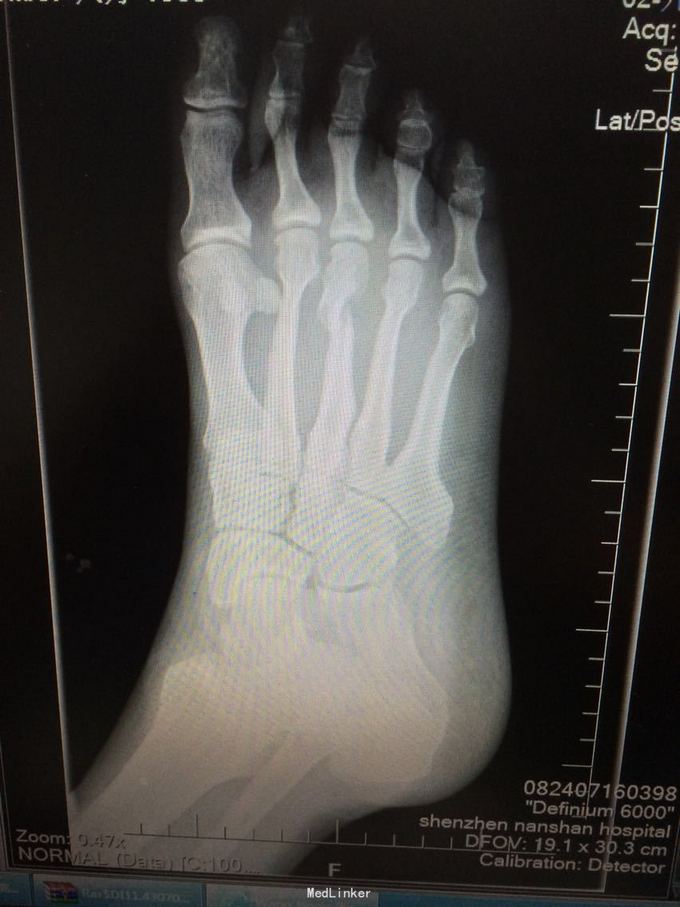

入院查体: T:37.2 摄氏度,P:85 次/分,R:18次/分,BP:129/85mmHg,神志清楚,生命体征平稳,自动体位,头颅无畸形,五官端正,頚软,无抵抗,心、肺、腹未发现明显异常,肛门生殖器未检。脊柱无侧弯、后突畸形,各棘突无压痛、叩击痛,活动正常。右足肿胀,畸形,右足背中远段可见一伤口,周围覆盖血痂组织,局部皮肤淤青,局部压痛明显,纵向叩击痛,可触及骨擦感及异常活动,右足活动受限,右足趾末梢血运正常,感觉存在。 4.辅助检查: X线片提示:右足第3跖骨远端骨折,断端移位。

右足第3跖骨远端骨折;2.右足背皮肤软组织严重挫擦伤 1、中年男性患者,右足明显外伤史。 2、专科情况:右足肿胀畸形,右足背中远段可见一伤口,周围覆盖血痂组织,局部皮肤淤青,局部压痛明显,纵向叩击痛,可触及骨擦感及异常活动,右足活动受限。 3、X线片提示:右足第3跖骨远端骨折,断端移位。 该患者有明确有外伤史,根据入院临床查体及辅助检查结果,诊断明确,无需鉴别。